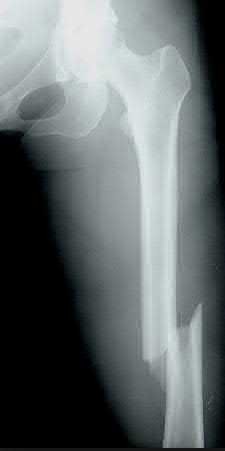

Question 3:

A 15-year-old boy presents with a permeative lytic lesion in the femoral diaphysis with aggressive periosteal reaction ('onion skinning'). Biopsy reveals uniform small round blue cells. Cytogenetic analysis of this tumor will most likely demonstrate which of the following translocations?

Correct Answer: t(11;22)

Explanation:

The clinical and radiographic description is classic for Ewing sarcoma. The characteristic cytogenetic abnormality is a balanced translocation t(11;22)(q24;q12), which fuses the EWS gene on chromosome 22 with the FLI1 gene on chromosome 11. This is seen in approximately 85-90% of Ewing sarcomas. t(9;22) is the Philadelphia chromosome (CML), t(X;18) is seen in synovial sarcoma, t(2;13) in alveolar rhabdomyosarcoma, and t(12;16) in myxoid liposarcoma.